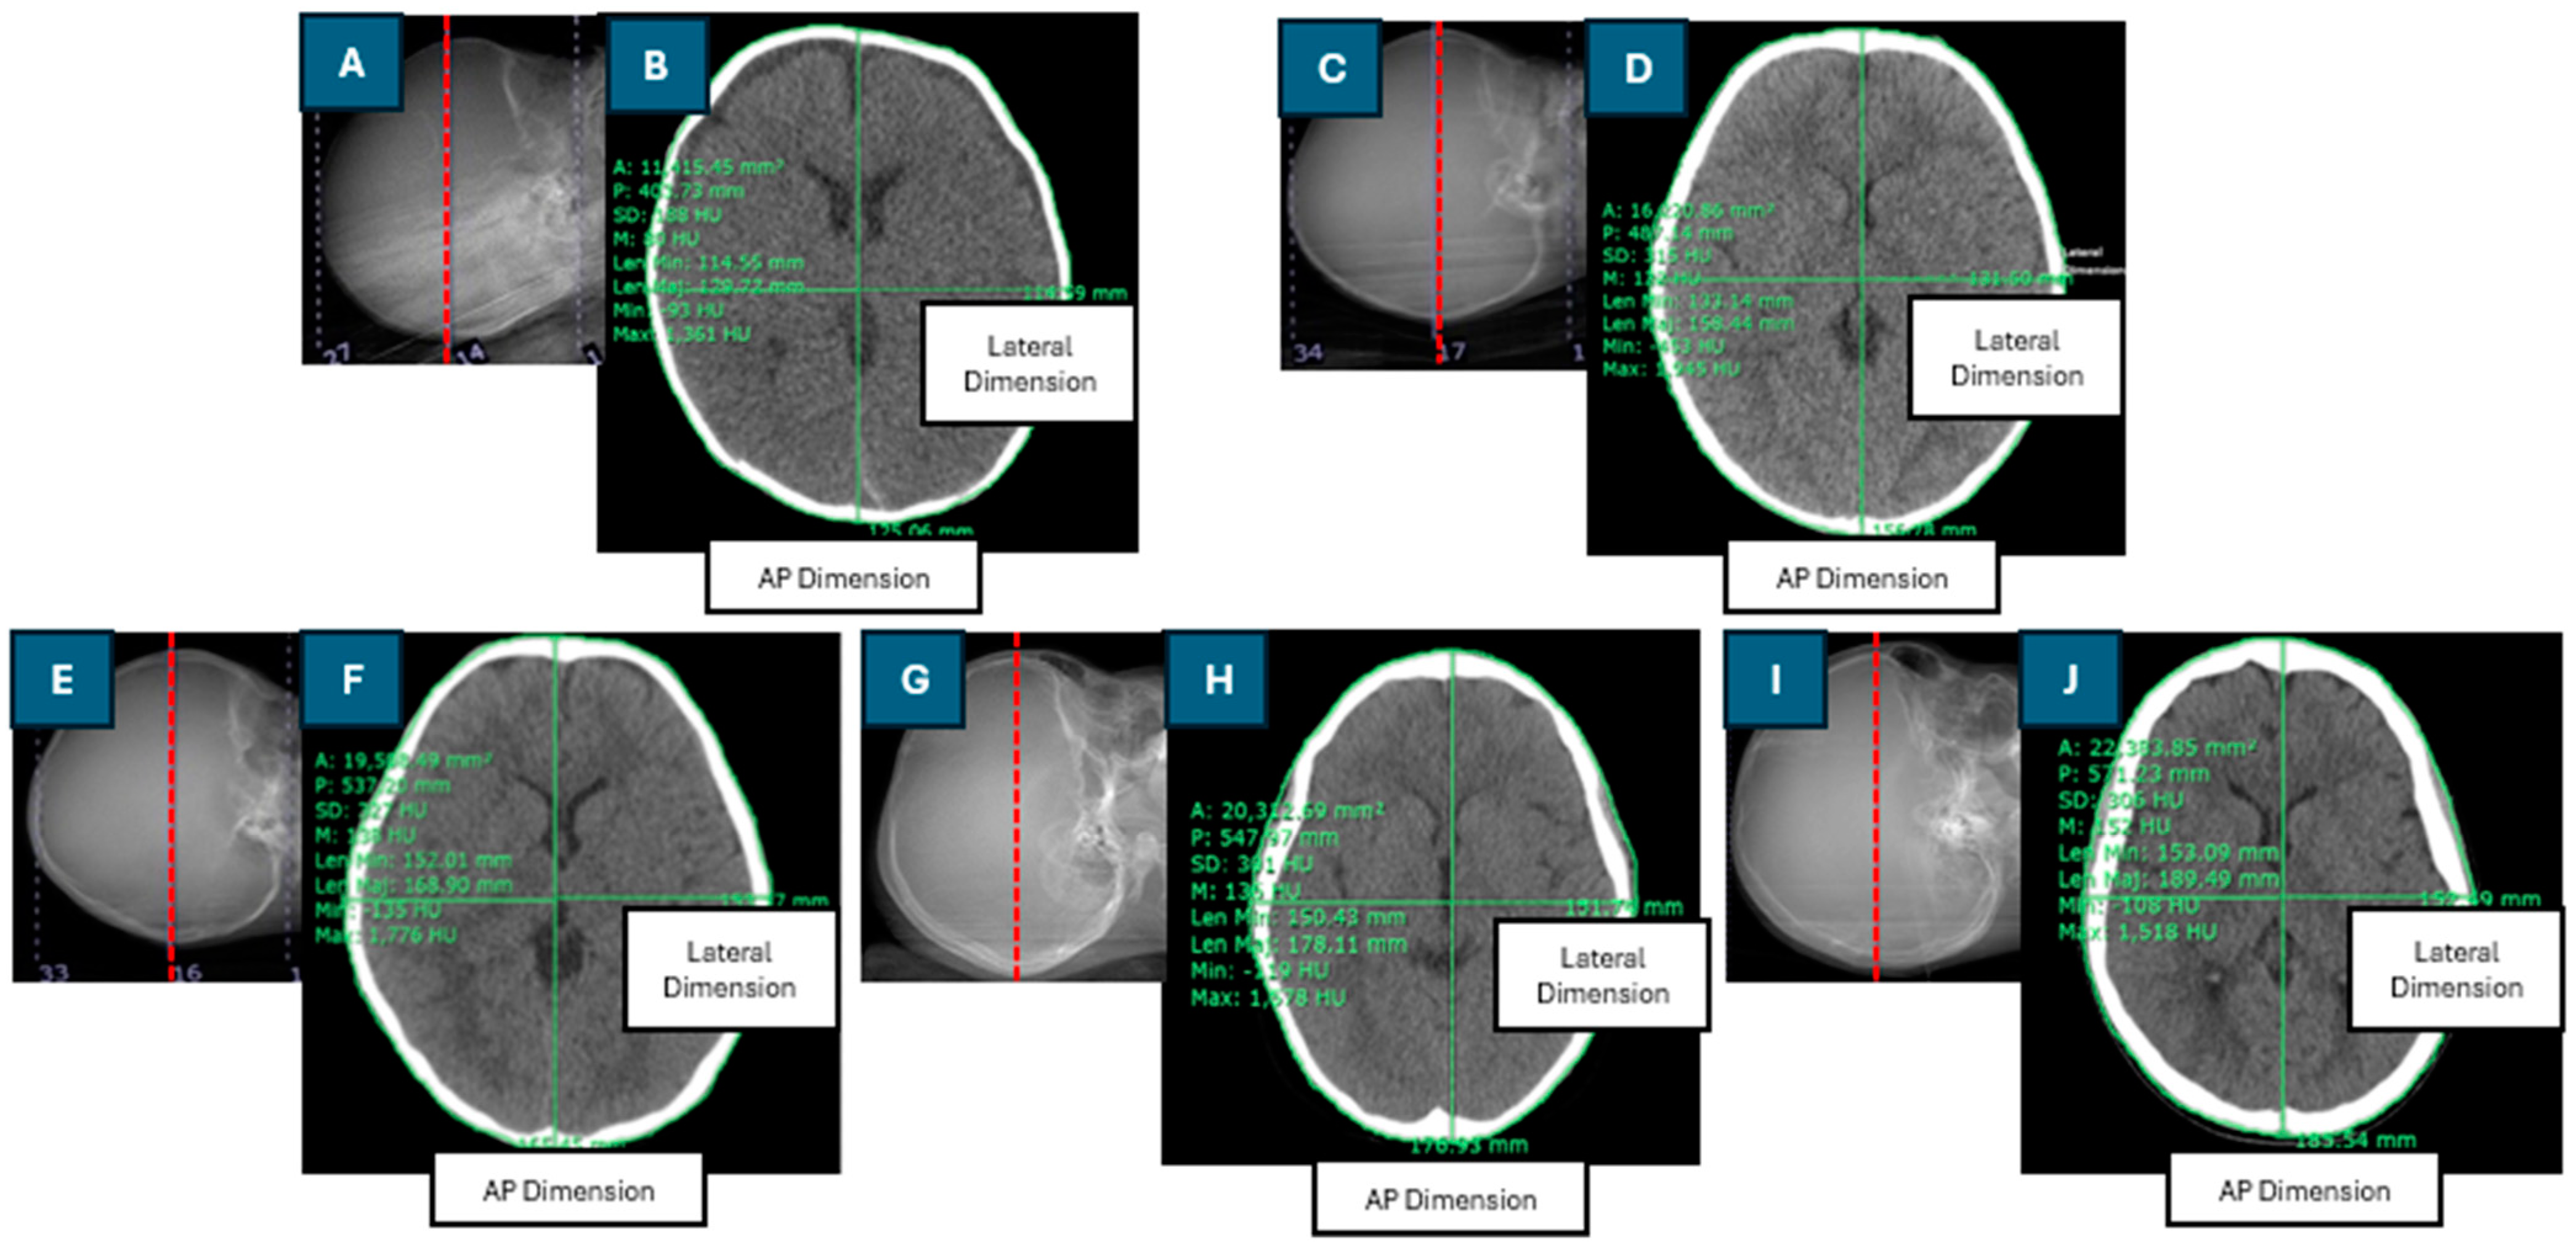

Figure 2 shows a box plot of the mean CT numbers within the ROI (HU) across the five age groups. The median value for the 0-to-6-month age group was lower than that of the other age groups. The median value for the 6-month-to-3-year age group was slightly lower than that for the 3-to-6-year age group. However, the median value for the 6-to-12-year age group was lower than that for the 6-month-to-3-year and 3-to-6-year age groups. The 12-to-15-year age group exhibited the highest median value of the mean CT number within the ROI.

Figure 2 shows that the median mean CT number in the ROI (HU) for the 6-to-12-year age group was lower than that for the 6-month-to-3-year and 3-to-6-year age groups. This is primarily due to a higher incidence of hypodense lesions and hydrocephalus in pediatric patients aged 6 to 12 years, which contributes to lower mean CT numbers. Notably, there were outliers in the 6-to-12-year and 12-to-15-year age groups, with mean CT numbers of 50 HU and 43 HU, respectively, which were attributed to specific clinical conditions: bilateral subdural fluid collection and pneumocephalus in the former case, and multiple pneumocephalus and moderate hydrocephalus in the frontal lobe in the latter.